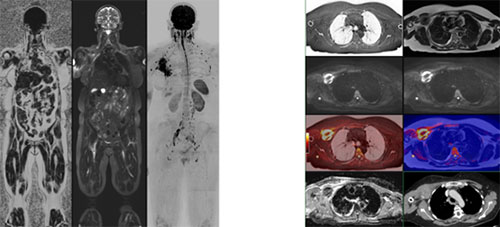

Whole-Body Diffusion-weighted Imaging (WB-DWI) provides unique functional insights into tissue properties, primarily by assessing the mobility of water molecules. This allows for an "at-a-glance" assessment of both normal tissues and the burden and distribution of disease. It is worth stressing that WB-DWI is just one, but still the key one, of several sequences deployed in the WB-MRI examinations. The way these other sequences are used depends on the application (Table 1). Modern imaging analysis uses displays of multiple functional imaging sequences, maximum intensity projection (MIP) displays, and image fusions (Figure 2) all correlated with morphological CT and PET/CT scans.

Figure 2: 52F. Invasive Lobular Cancer. ER+, PR+, HER2-. Axillary recurrence of disease 6 years post-mastectomy. Left figure: coronal T1-weighted fat fraction, STIR, and b900 MIP (inverted grey scale) images showing the extent of craniocaudal coverage. There is a larger volume of right axillary nodal and chest wall disease, as well as right arm lymphoedema. Pelvic nodal disease on the right and left hydronephrosis. Right figure. Left column: black bone (inverted scale), b900, and fused images with the corresponding ADC map. Right column: T2W, b900, fused and corresponding contrast-enhanced CT scan at the same level.

The strength of WB-DWI in characterization lies in combining the signal intensity of diffusion-weighted information with ADC values, which function as a biomarker of cellularity. High cellularity tissues, including tumors, appear bright on high b-value images, while areas of impeded diffusion appear darker on grayscale ADC maps. An inverse correlation exists between ADC and cell density in many malignant tumors. However, in bone marrow, ADC correlations with cellularity are often non-inverse. The phenomenon is related to the mixed fat-cell population within a fixed bone marrow space. The characterization of tissues is further enhanced by combining DW-MRI information with morphologic images, fat imaging made possible by Dixon images, and black bone sequences, all of which can be done in a time-efficient whole-body basis on modern scanners (Figure 2).